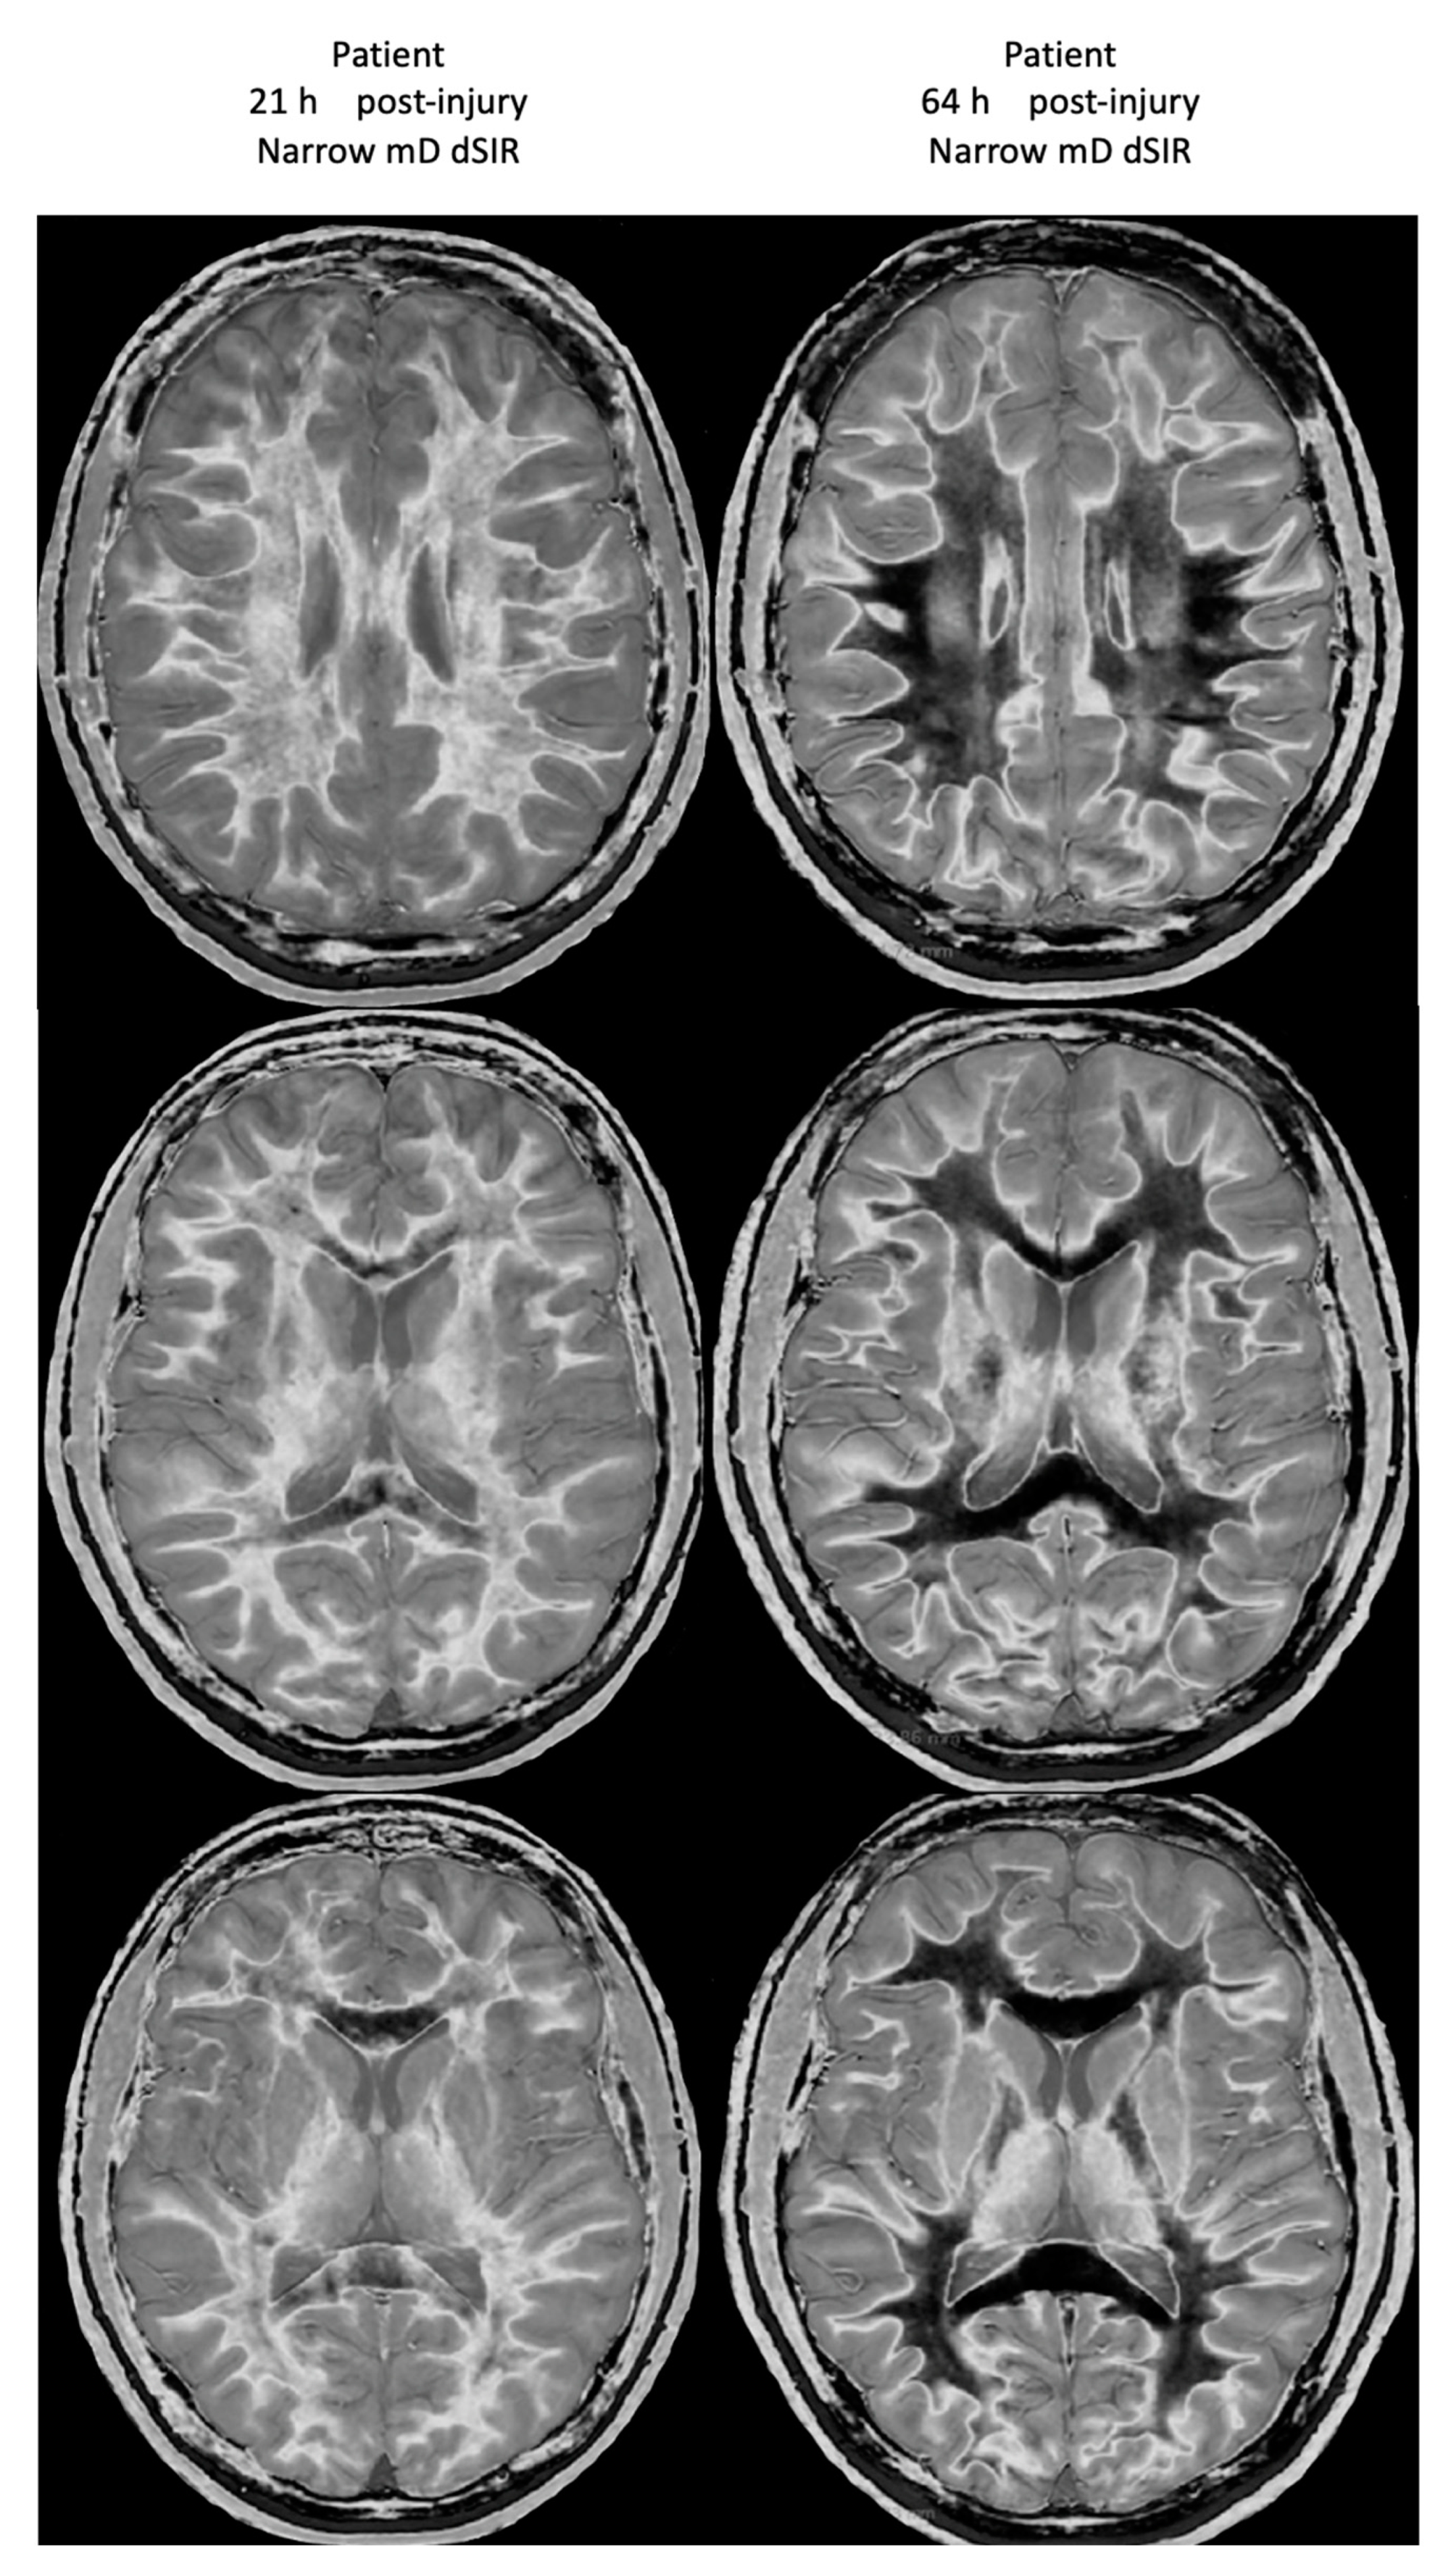

Figure 21 shows his dSIR images at 21 h post-injury (left column) and at 64 h post-injury (right column). There is a marked difference between the dSIR images at 21 h (left column) and 64 h (right column) consistent with complete regression of his whiteout sign over 43 h (i.e., in just less than two days) from grade 4 to grade 1. Case 2’s 64 h post-injury dSIR images (right column) are similar to the normal control images shown in Figure 16.

Figure 21.

Case 2 Acute mTBI imaged 21 h and 64 h post-injury. Narrow mD dSIR images. On the images obtained at 21 h post-injury, extensive high signal abnormalities are seen in most of the white matter with sparing of the anterior and posterior central corpus callosum and peripheral white matter of the cerebral hemispheres (left column). On the images at 64 h post-injury, normal low signal white matter is seen in the hemispheres (right column). The images show marked regression of abnormalities over 43 h (i.e., just less than two days). The boundaries between white and gray matter and around the lateral ventricles become more obvious after regression of whiteout sign from grade 4 (left column) to grade 1 (right column).

No abnormality was seen on Case 2’s T2-FLAIR images either at 21 h or 64 h post-injury.